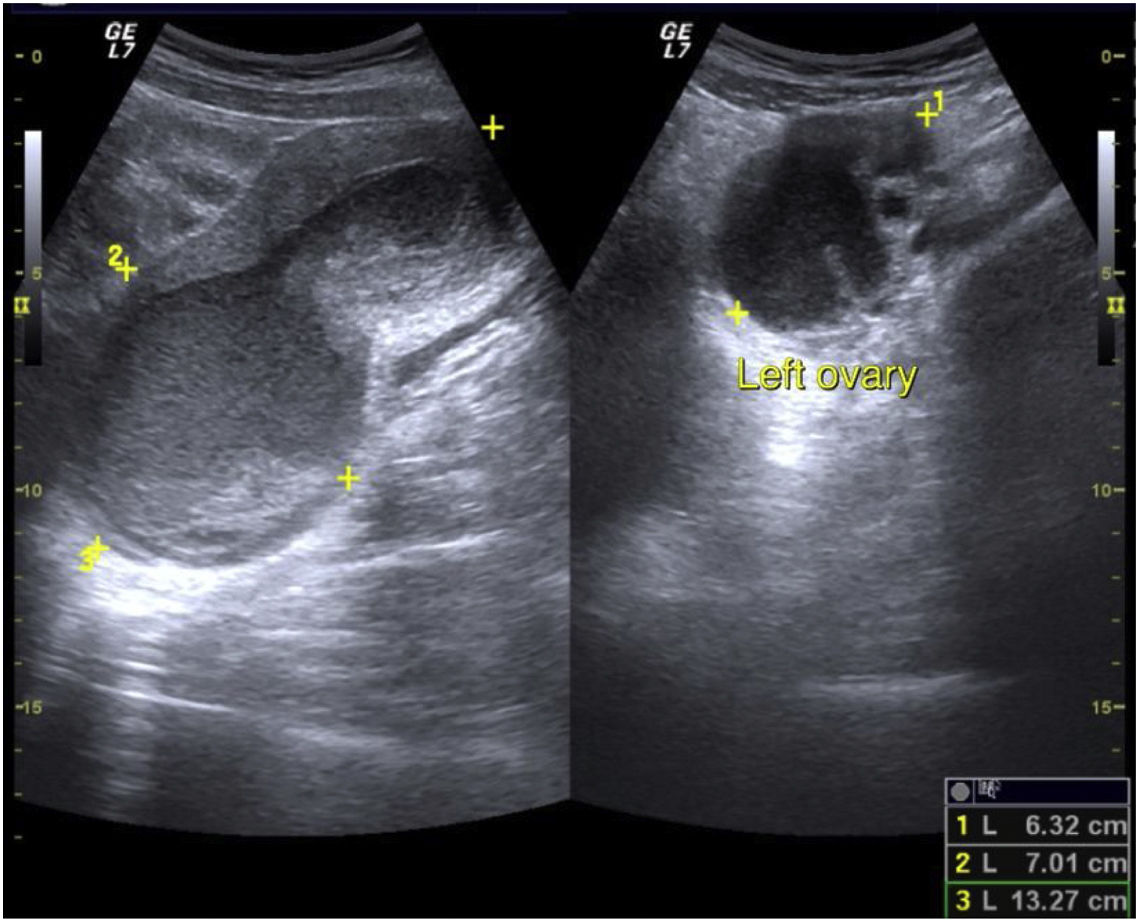

Datos clínicosNiña de 12 años de edad con cuatro episodios de dolor abdominal en los últimos 4 meses.

Pregunta 1Describa los hallazgos radiológicos.

(Pregunta de texto libre, no se proporciona opción de respuesta.)